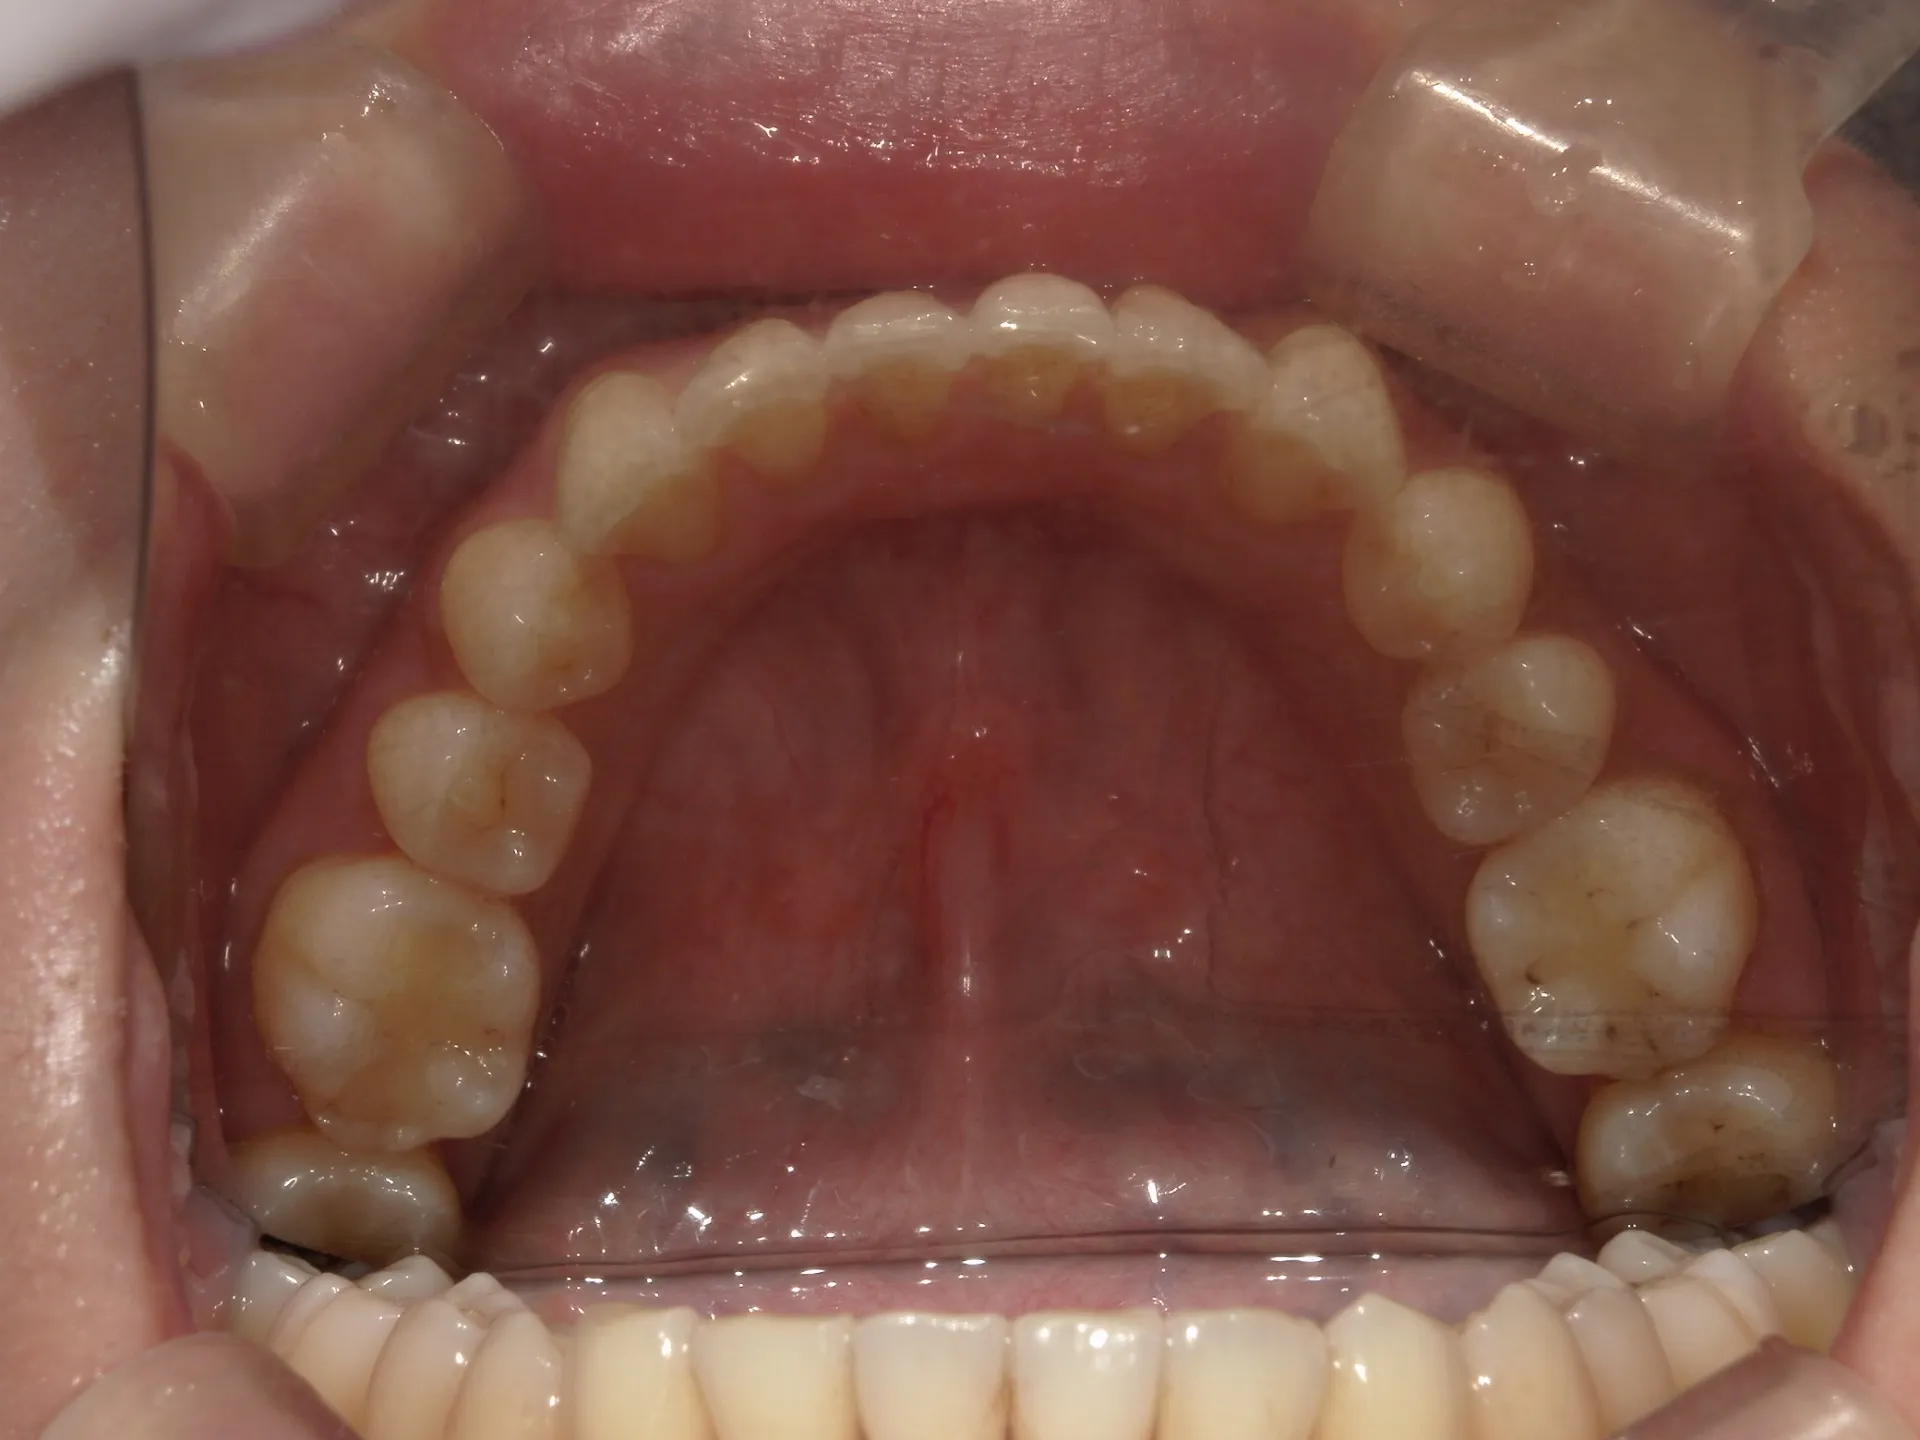

正面観

初診時

上の前歯が1本大きくねじれ、更にその歯に変色も見られました。

下の歯もスペースがなくガタついている状態の歯並びでした。